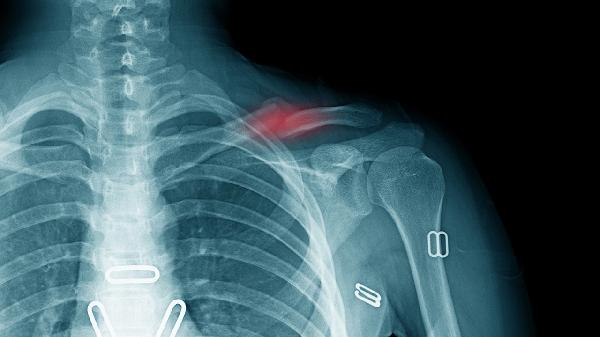

左鎖骨上淋巴結(jié)腫大可能由感染、結(jié)核、惡性腫瘤轉(zhuǎn)移、免疫系統(tǒng)疾病或反應(yīng)性增生等原因引起。主要有上呼吸道感染、淋巴結(jié)結(jié)核、胃癌轉(zhuǎn)移、淋巴瘤、系統(tǒng)性紅斑狼瘡等因素。

左鎖骨上淋巴結(jié)是胃癌常見的轉(zhuǎn)移部位,稱為Virchow淋巴結(jié)?;颊呖赡苡邢?、腹痛、黑便等原發(fā)灶癥狀,淋巴結(jié)活檢可明確診斷。治療需根據(jù)分期選擇手術(shù)、化療或靶向治療,如奧沙利鉑注射液、卡培他濱片、曲妥珠單抗注射液等。日常需少食多餐,選擇易消化食物。